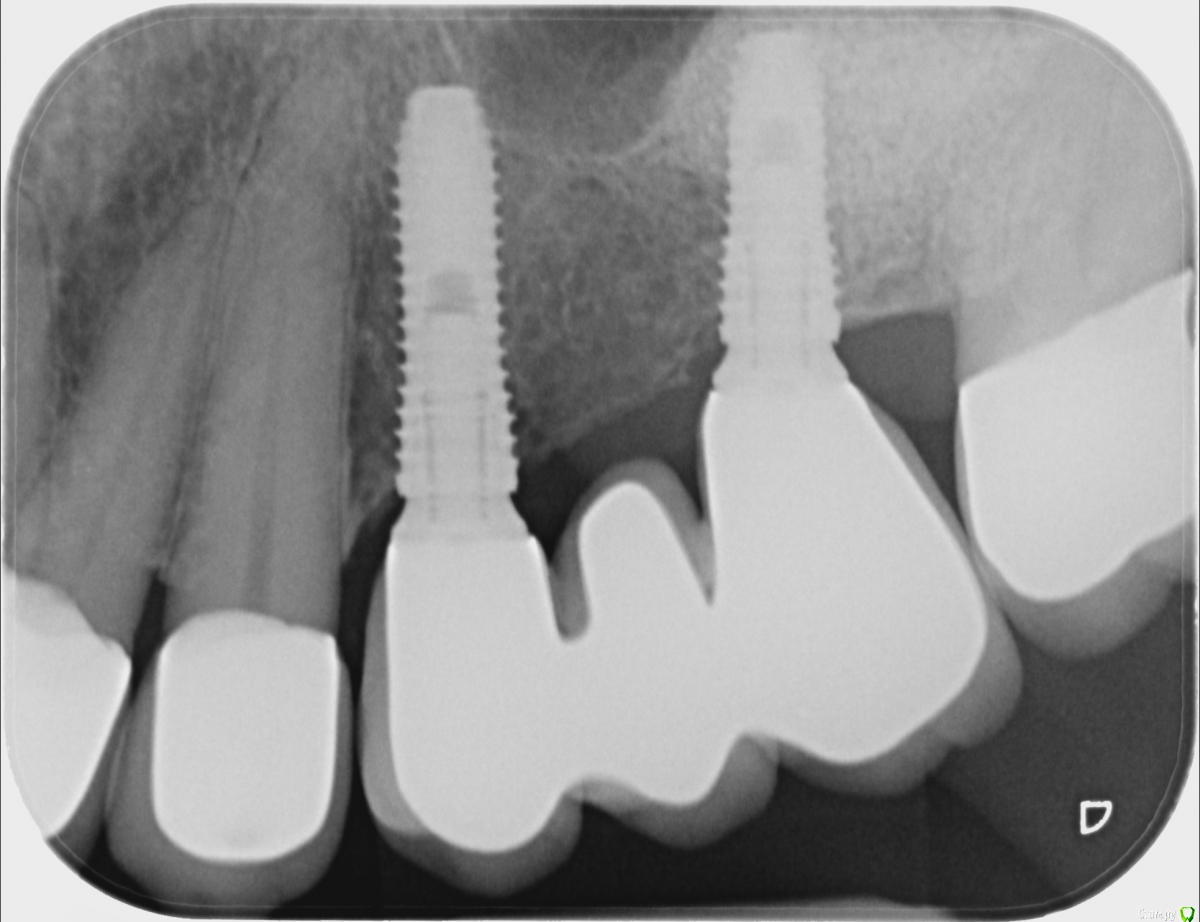

ellenchik Опубликовано 7 февраля, 2019 Поделиться Опубликовано 7 февраля, 2019 Добрый день, имплантант стоит 3 года.( DIO-имплантант). Последнее время-неясные жгучие ,ноющие боли по левой стороне верх.челюсти. Искали причину в зубах под коронкой. По последнему прицельному снимку стоматолог увидела воспаление возле имплантанта.. Имплантолог к сожалению в другой стране. Придется лететь туда или искать другого специалиста на месте ? Спасибо большое за комментарии. С уважением Елена. Ссылка на комментарий

red_butler Опубликовано 7 февраля, 2019 Поделиться Опубликовано 7 февраля, 2019 не вижу проблем с имплантами 6 Ссылка на комментарий

Бендер Опубликовано 8 февраля, 2019 Поделиться Опубликовано 8 февраля, 2019 Проверяйте соседние зубы Ссылка на комментарий